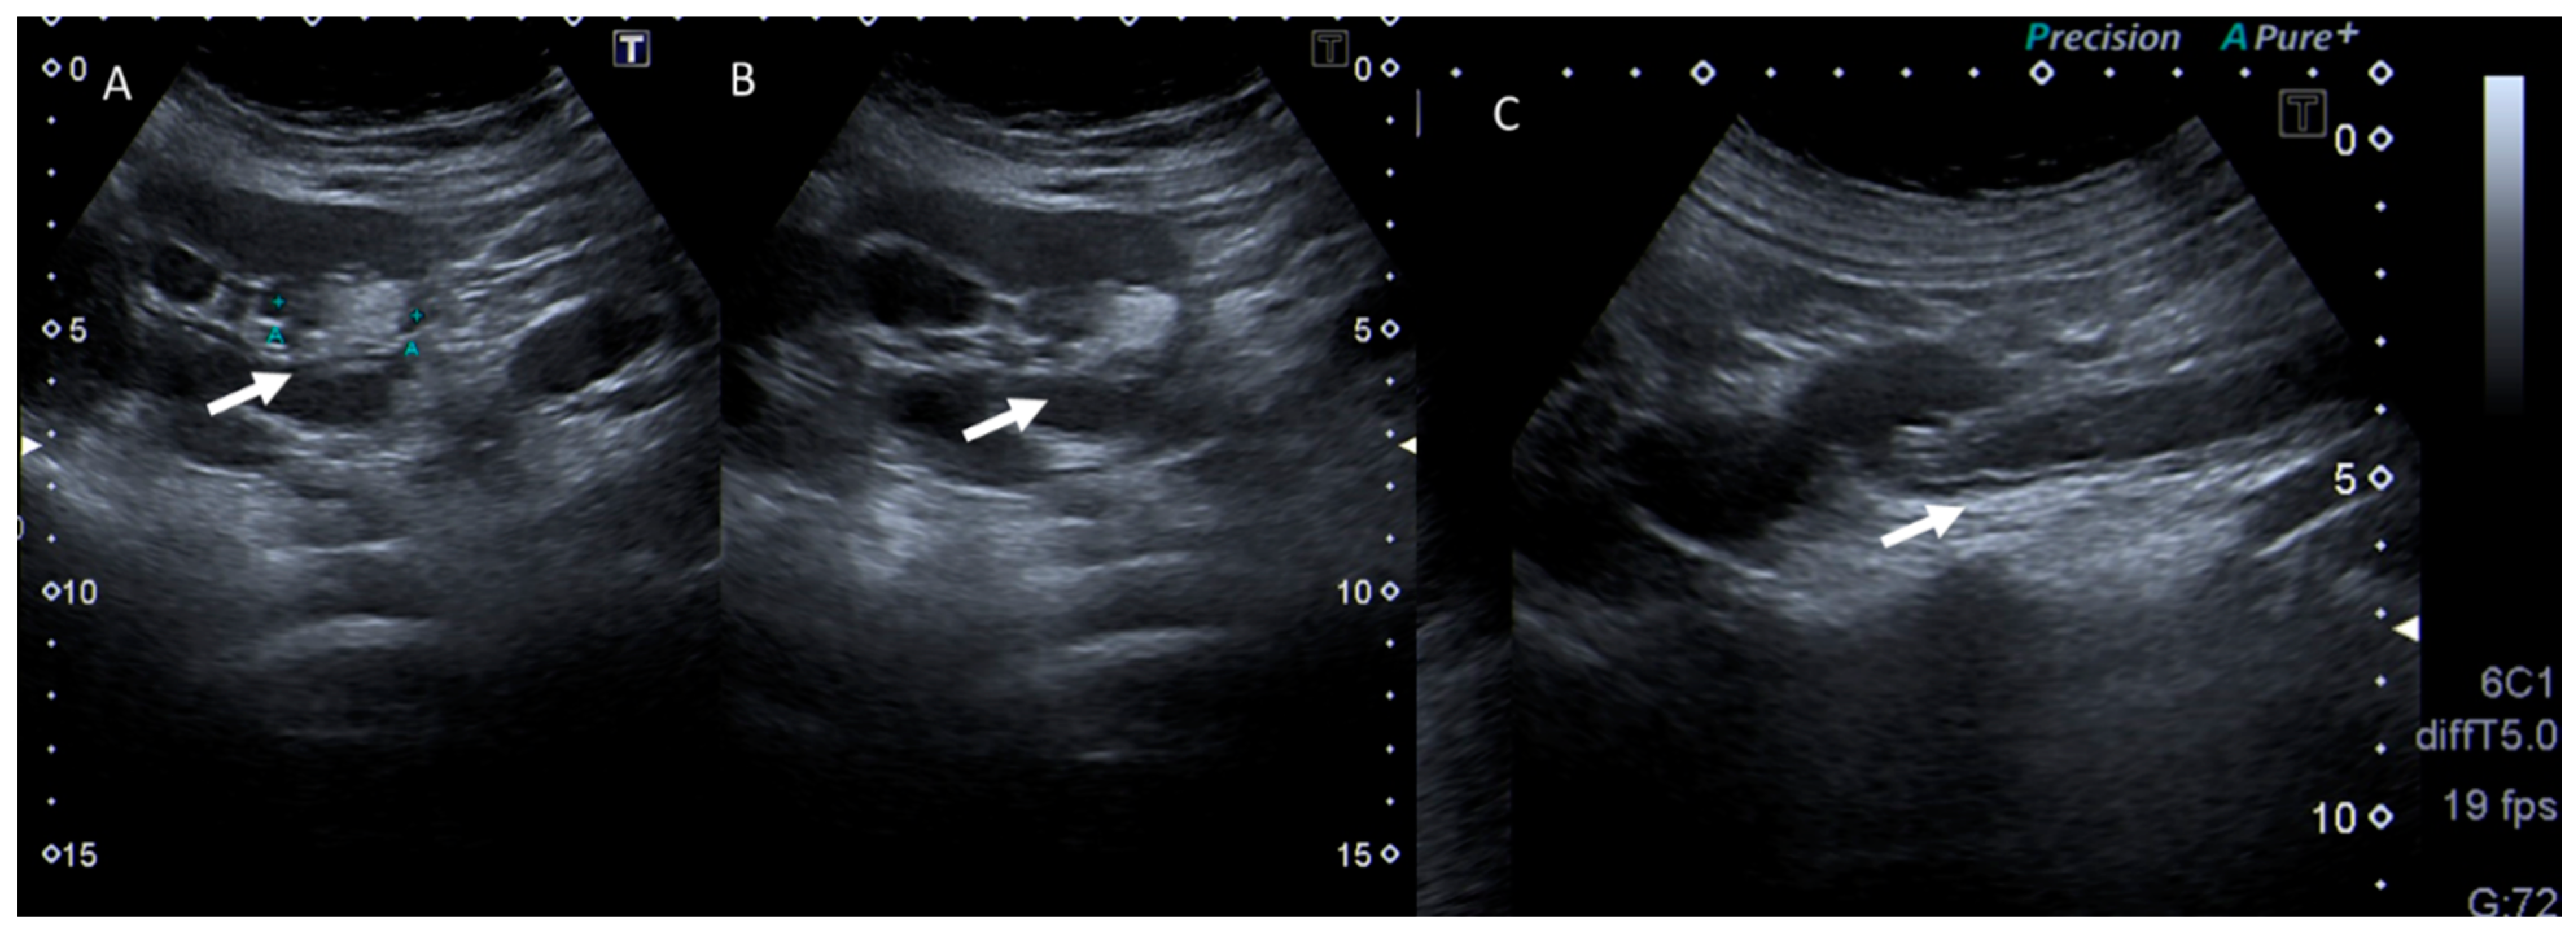

6. Biliary Tract and Pancreatic Diseases

7. Ureterolithiasis